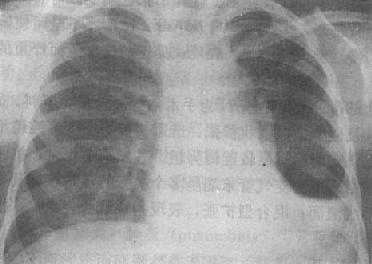

气胸的X线表现是由于胸腔内气体将肺压缩,使被压缩肺与胸壁间出现透明的含气区,其中不见肺纹理(图3-1-16)。肺被压缩的程度与胸腔内气体多少成正比。气体首先自外围将肺向肺门方向压缩,被压缩肺的边缘,呈纤细的线状致密影,呼吸时清楚。大量气胸可将肺完全压缩,肺门区出现密度均匀的软组织影。纵隔可向健侧移位,患侧膈下降,肋间隙增宽。张力性气胸时,可发生纵隔疝。健侧肺可有代偿性肺气肿。发生胸膜粘连,可见条状粘连带影。多处粘连,可将气胸分隔为多房局限性气胸。

图3-1-16 右侧气胸伴右下胸膜粘连

右肺萎陷,向肺门收缩,密度高,压缩肺与胸壁间

透明,其中未见肺纹理,肺底有粘连带与膈相连